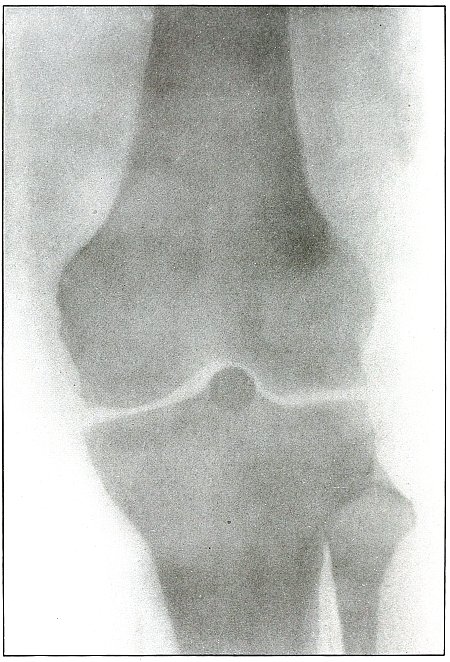

| 59. |

Gunshot wound, knee |

128 |